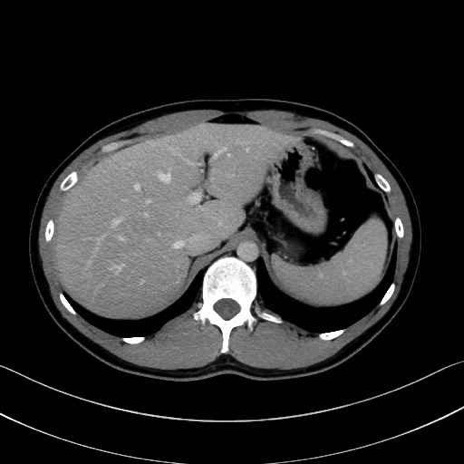

腰方形筋(quadratus lumborum muscle)のCT画像の解剖

1. 体幹部(腹部・背部・後腹壁)の筋肉

腹直筋 (Rectus abdominis)

外腹斜筋 (External oblique)

内腹斜筋 (Internal oblique)

腹横筋 (Transversus abdominis)

腰方形筋 (Quadratus lumborum)

広背筋 (Latissimus dorsi)

脊柱起立筋 (Erector spinae)

多裂筋 (Multifidus)